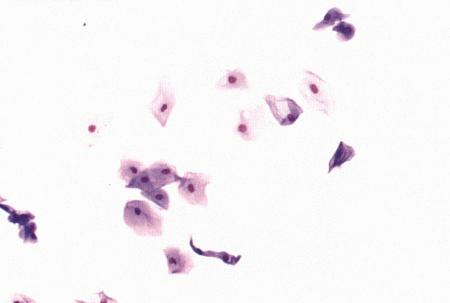

Фиг. 3.4.

Поверхностные клетки в мазке вагинальных выделений у суки в период эструса (окрашивание мазка Schorr's trichrome).